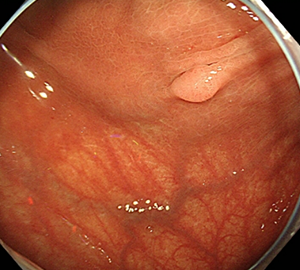

コールドスネアポリペクトミー(CSP)

合併症の非常に少ない優れた治療法であることから、近年大腸ポリープの外来切除法として急速に施行件数が増えてきています。当院ではこのコールドスネアポリペクトミーを主体としたポリープ切除を行っています。

![]() |

|

| 1:ポリープを見つけます。 | 2:狭帯域光画像併用拡大観察で詳細に観察します。 | |

| 3:病変をスネアに通します。 | 4:周囲の正常粘膜をしっかり入れながら、病変を絞扼していき... | |